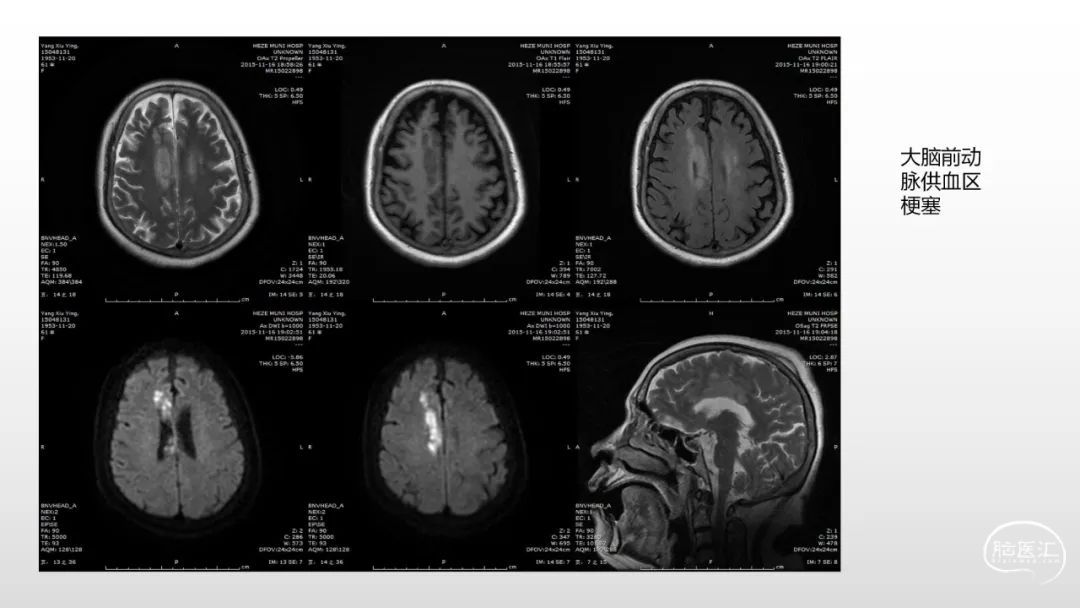

颅脑影像诊断基础知识讲座:感染和免疫性疾病1